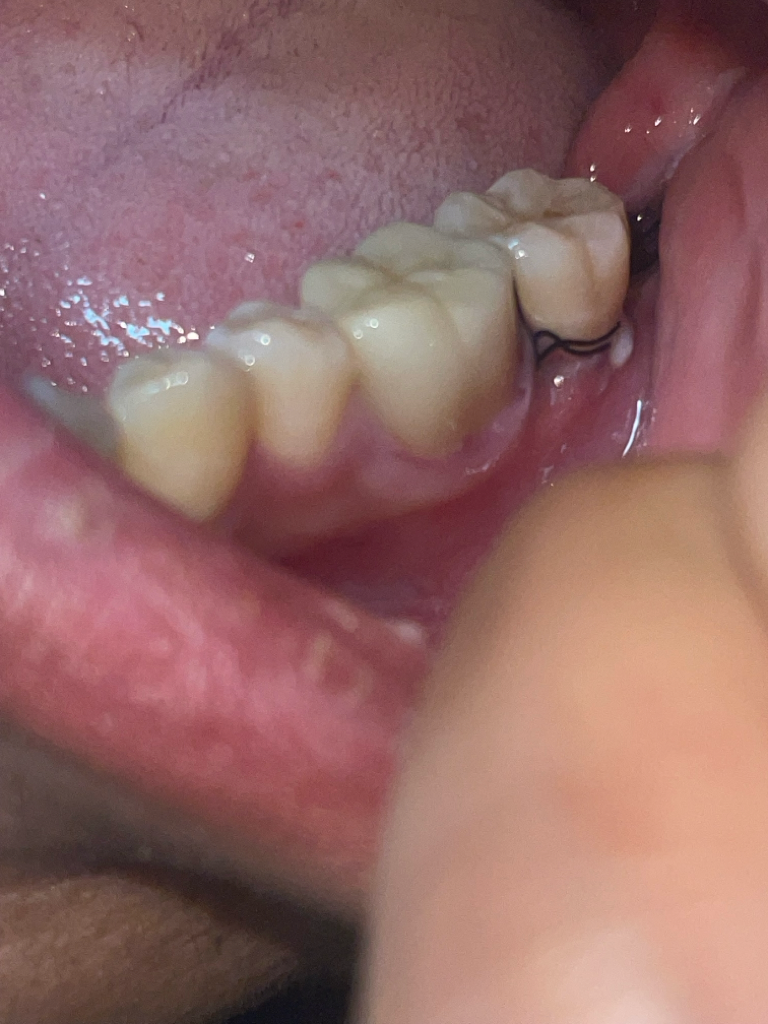

매복사랑니 발치후 혈병이 빠지면 병원을 가봐야할까요?(사진첨부)

안녕하세요 어제 11시경 사랑니 발치후 24시간 정도가 지났습니다 통증은 마취풀렸을때 이후 큰통증은 없지만 혈병자리를 확인하다가 이게 빠진건지 어떤상태인건지 모르겠어서 질뭉드립니다. 안에 실밥이 보이는데 혈병이 떨어져서 실밥이 보이는걸까요?

• 1번 째 사진

현재 사진상 문제가 되어 보이지 않으며 잘 아물고 있는 것으로 보이기에 치과에 방문하지 않으셔도 됩니다. 해당부위에 염증이 덧나지 않게 헥사메딘 가글액으로 가글을 하고, 흡연 및 음주는 7일간은 피하길 권합니다.

1. 봉합실은 원래 보이는 것이 맞습니다.

2. 혈병은 1~2일차에 잇몸 상피세포로 바뀌므로 혈병이 탈락하거나 그런 것이 아니라 자연스러운 치유 과정일 수 있습니다.

3. 발치 후 주의사항 잘 지키면 치유에 아직까지는 큰 문제는 없을 것 같습니다.